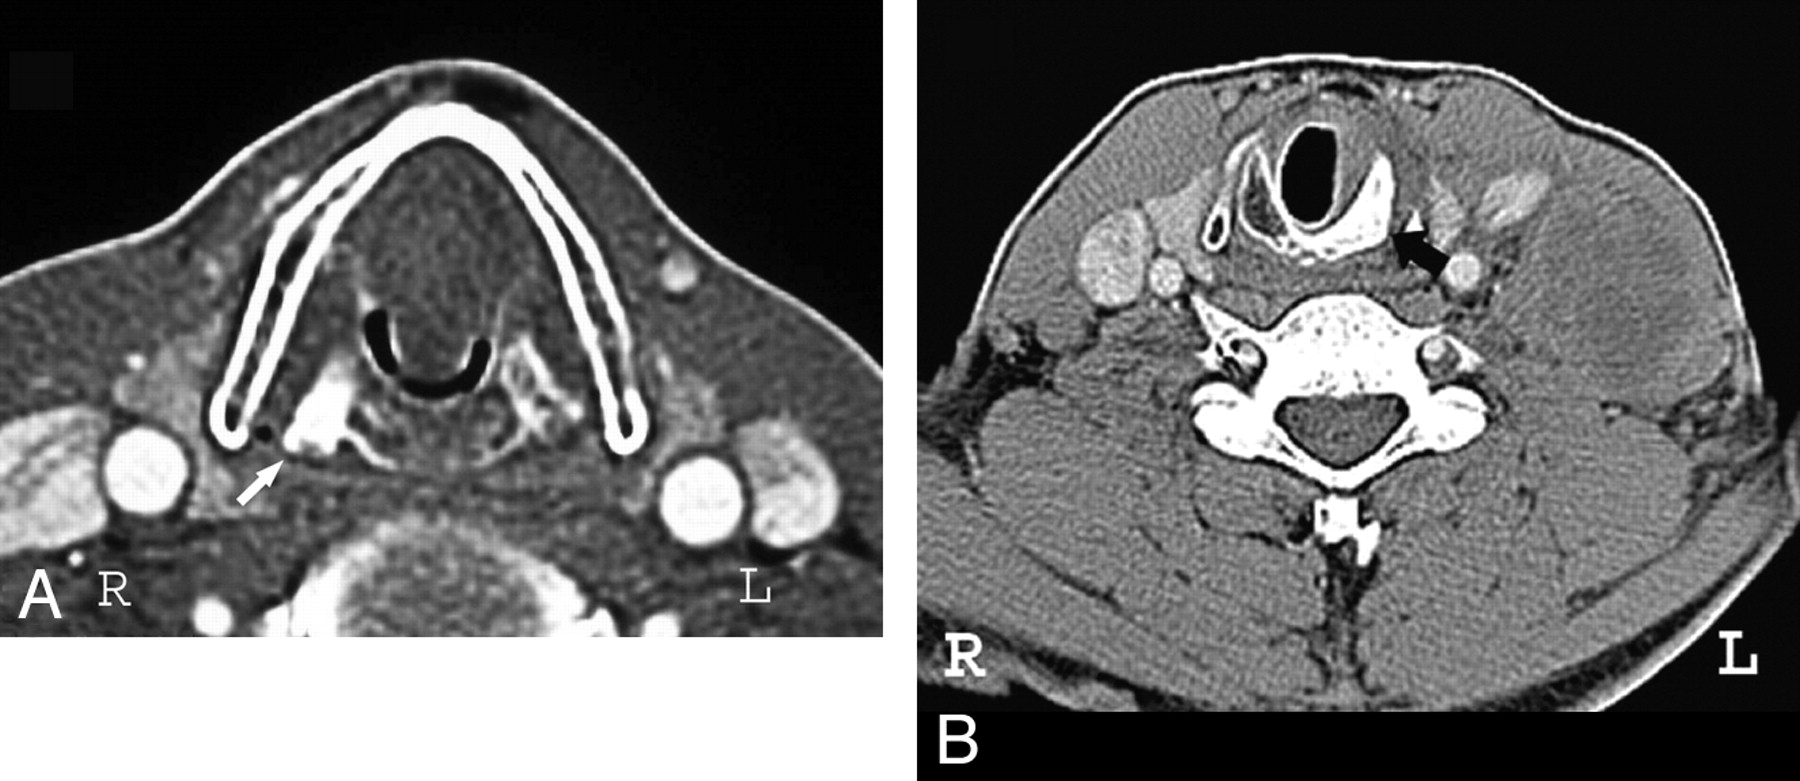

What structure is the white arrow on the left pointing to?

Cricoid

Where is the Cricoid in relation to the Thyroid

Right below thyroid

Thyroid vs. Cricoid, anatomically

Thyroid is right above thyroid - Looks like “^”

Cricoid comes in right underneath it, like a “u”